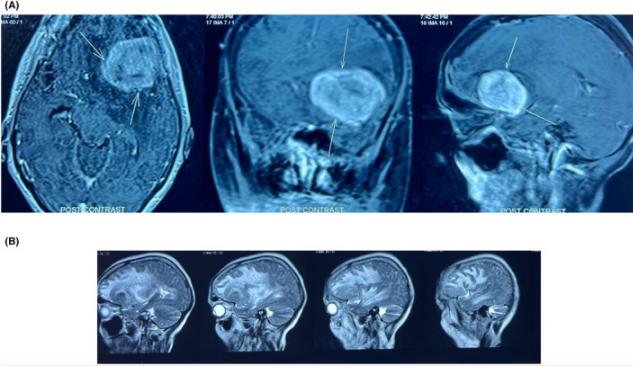

重复进行MRI扫描,显示与上次扫描相比,病变尺寸增大,由于肿块进一步增大,两处病变可能融合,左侧脑室出现明显肿块效应,大脑中线向右移动5 mm,右侧大脑中动脉(MCA)皮质分支在病变中间发生位移。肿块在T1加权像上呈低信号,在T2加权像上呈高信号。CT灌注研究显示在左侧外侧裂的后部有一个边界清晰的高密度轴外病变(图1A)。病变显示出非常高的灌注,脑血容量、流量增加,平均通过时间减少。

图1、A和B: CT扫描显示左侧外侧裂后侧边缘良好的高密度轴外病变